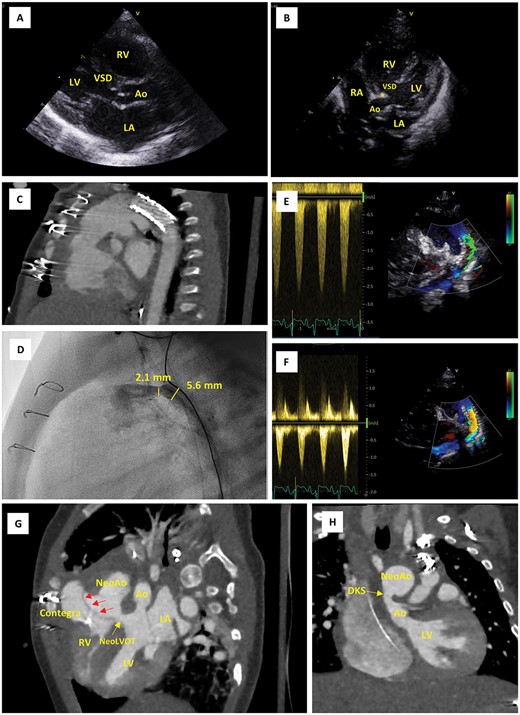

Imaging findings. (A) Parasternal long-axis echo view on postnatal Day 0, showing the large VSD and narrow native LVOT (5.0 mm in this view). (B) Apical five chamber echo view on postnatal Day 0, showing posterior displacement of the conal septum (*) and the narrow native LVOT (3.7 mm in this view). (C) CTA scans after first cardiac catheterization at the age of 12 days, showing position of the ductal stent. (D) Emergency cardiac catheterization at the age of 2 months, showing restenosis of the (non-stented part of the) proximal duct (30 mmHg, diameter 2.1 mm). (E, F) Pulsed wave Doppler evaluation of ductal flow, showing flow acceleration up to 2.5 m/s when the patient was stabilized at the PICU prior to emergency cardiac catheterization (E) and reduction of this flow acceleration to <1.5 m/s following resolution of the stenosis using a Formula 535 vascular balloon-expandable stent (F). (G, H) CTA scan after Yasui procedure; modified views to demonstrate the Rastelli tunnel (red arrows) and the narrow native aortic valve (Ao) (G) as well as the DKS anastomosis (H). Ao, aorta; CTA, computerized tomography angiography; DKS, Damus–Kaye–Stansel; LA, left atrium; LV, left ventricle; PICU, pediatric intensive care unit; NeoAo, neo-aorta; RA, right atrium; RV, right ventricle; VSD, ventricular septal defect.

A female newborn, delivered at 39 weeks and 3 days’ gestational age (birth weight 3.4 kg), was admitted to the neonatal intensive care unit (NICU) of our tertiary referral center for planned postnatal care (Table 1). Amniocentesis had revealed 22q11.2 microdeletion and fetal echocardiography allowed for prenatal diagnosis of IAA type B and large inlet VSD with extension to the outlet and posterior displacement of the conal septum resulting in LVOTO. Prostaglandin E1 infusion was immediately instituted. Echocardiography at this point revealed a small, oval shaped LVOT with dimensions 5.0 × 3.7 mm (Fig. 1A and B). The VSD measured 9 mm, whereas the diameters of the aortic valve annulus, sinus of Valsalva and sinotubular junction were 5.2 mm (Z-score − 3.1), 7.6 mm (Z-score − 2.5) and 6.3 mm (Z-score − 1.7), respectively [8]. In addition, the diagnosis of an aberrant right subclavian artery (arteria lusoria) was made, thus indicating IAA type B2.

During a multidisciplinary meeting the decision was made to pursue initial hybrid palliation consisting of PAB and ductal stenting, followed by delayed biventricular repair using a Yasui-type operation. This strategy would avoid high-risk neonatal surgery and in the meantime allow for potential growth of the LVOT. Ductal stenting was completed at the age of 12 days. A sinus-SuperFlex-DS stent was positioned in the arterial duct using a soft coronary wire (Fig. 1C). The procedure was uncomplicated and the patient could be discharged home at the age of 23 days.

At 2 months of age, the patient was re-admitted at the emergency department with increased crying, pallor, vomiting and diarrhea. The child was noted to have tachypnea, tachycardia, hepatomegaly by 3–4 cm below the costal margin and dry mucosae. Saturation was 95% at admission but later decreased to 86%. The NT proBNP level was 33 000 pg/ml. Echocardiography revealed a poor systolic right ventricular (RV) and LV function and stenotic flow through the ductal stent. The patient was admitted to the pediatric ICU (PICU) for support with fluids, milrinone, adrenaline and mechanical ventilation, and was subsequently prepared for cardiac cathetherization. In the cathlab, restenosis of the proximal duct (30 mmHg, diameter 2.1 mm) was identified and resolved with a Formula 535 vascular balloon-expandable stent (Fig. 1D–F). The immediate postinterventional course was favorable, although NT proBNP initially remained high and LV function was still moderate. After 10 days, the patient could be transferred from the PICU to the pediatric cardiology ward.

At the age of 3 months, while still in the PICU, the patient underwent a Yasui-type procedure to complete the two-stage biventricular repair (Fig. 1G–H). The procedure was performed via median sternotomy with cardiopulmonary bypass, using the brachiocephalic artery and the duct for arterial cannulation and the right atrium and inferior vena cava for venous cannulation. The duct, arch and arch arteries were dissected free, taking care not to injure the left laryngeal recurrent nerve. Following clamping of the ascending aorta and administration of anterograde cardioplegia, a right atriotomy was performed. The left heart was decompressed through the atrial septal defect (ASD) and the arterial cannula was removed from the ductus. The ductal stent was then removed and the ductus was ligated at the pulmonary side. The pulmonary artery bifurcation was detached from the pulmonary trunk. The patient was cooled to 19°C and anterograde cerebral perfusion was initiated to protect the brain during arch repair. The descending aorta was anastomosed end-to-side to the left carotid artery and distal ascending aorta. A Damus–Kaye–Stansel (DKS) anastomosis was then performed. Arch repair was completed by anastomosing the pulmonary trunk and DKS to the remainder of the arch. Both subclavian arteries were sacrificed using clips without connecting them to the aorta. Although perfusion to the body was restored and the patient was gradually rewarmed, the distal anastomosis of a 12-mm Contegra conduit to the pulmonary artery bifurcation was created. A right ventriculotomy was made and the VSD was closed in a fashion similar to the Rastelli procedure, such that the LV would connect to the pulmonary and aortic valves. Through the right atriotomy, the anteroseptal commissure of the tricuspid valve was closed, thereby achieving only trivial residual tricuspid regurgitation, and the ASD was closed. Finally, the proximal anastomosis of the Contegra conduit was completed and the right atriotomy was closed. Then cardiopulmonary bypass was discontinued, hemostasis was achieved, pacemaker leads and drains were left in place, and the sternotomy was covered with a sterile plastic foil to pursue delayed sternal closure on postoperative Day 3.